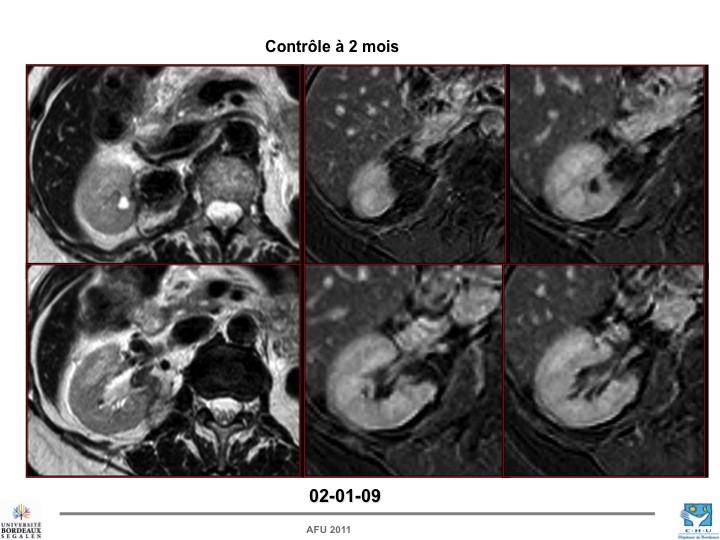

- Mini-débat : cas d’un patient âgé, surveillance vs traitement ablatif

Jean-Alexandre LONG (Grenoble) vs Jean-François HETET (Nantes)